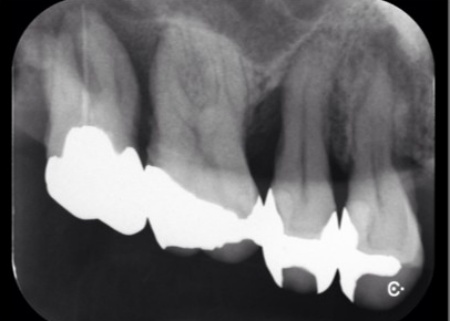

また、右下の奥歯3本は歯周病が重度まで進行していました。

レントゲンを撮影したところ、歯の周囲の骨が溶けて歯ぐきの深い部分にまで歯石が付着していることが確認できました。

また重度の歯周病が認められた右下の奥歯3本も歯周治療と再生療法を行い、口腔内の環境を改善する治療計画を説明しました。

右下の奥歯3本についても同様に、再生療法を行いました。

半年後のレントゲン検査では、失われていた骨の部分に新しい骨の形成が認められ、歯ぐきの腫れや出血も改善していました。